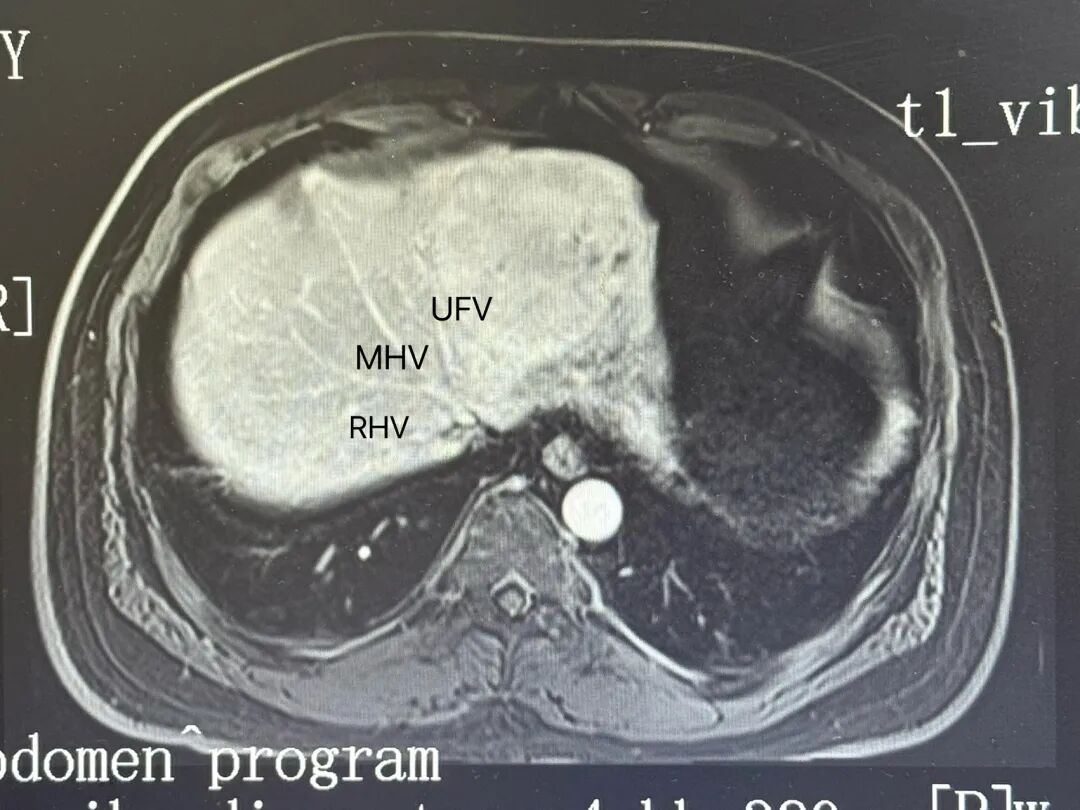

影像评估与手术规划:LHV没有显影,MHV、UFV完整,肿瘤位于矢状部左侧,P4ab完整。我的计划做左外叶可解决问题。